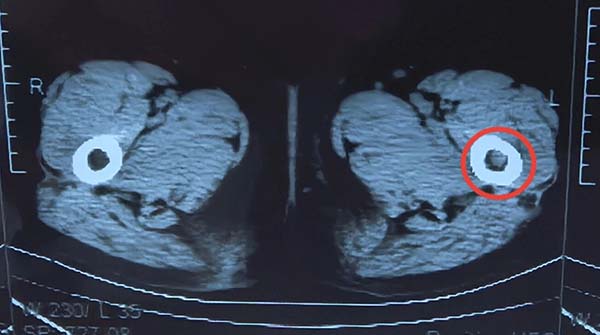

CT 扫描:骨质破坏特征显著;

骨扫描:左股骨代谢活跃,提示肿瘤活性。